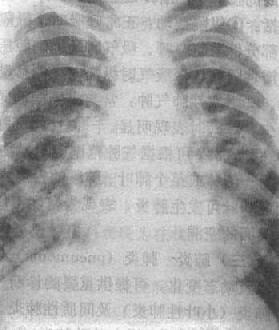

X线表现是病变多发生在两肺中、下野的内、中带。支气管及周围间质的炎变表现为肺纹理增多、增粗和模糊。小叶性渗出与实变则表现为沿肺纺理分布的斑片状模糊致密影,密度不均(图3-1-18)。密集的病变可融合成较大的片状。病变广泛可累及多个肺叶。小儿患者常见肺门影增大、模糊并常伴有局限性肺气肿。

图3-1-18 支气管肺炎

肺门影增大,肺纹理增强、模糊,中、下肺

野可见沿肺纹理分布的斑片状模糊致密影